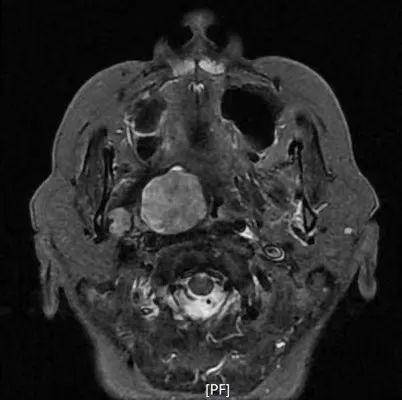

病例1:患者男,56岁,因反复鼻出血入院,入院CT、MRI示肿瘤侵犯右侧翼腭窝、颞下窝、翼突根及翼内外板。入院诊断:侧颅底恶性肿瘤。肿瘤范围大,难度大,风险高。

科室副主任刘永亮立即组织颅底肿瘤团队进行病例讨论,决定全麻经鼻内镜联合唇龈沟入路切除肿瘤,术中肿瘤完全切除。术后病理:(右侧鼻腔)纤维上皮瘤恶变为鳞状上皮原位癌。

CT、MRI示肿瘤侵犯右侧翼腭窝、颞下窝、翼突根及翼内外板